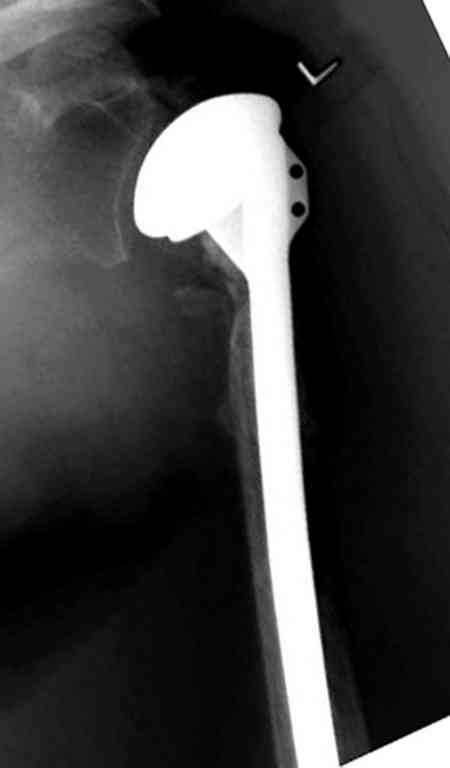

По Neer операцию рекомендовали только тогда, когда угол между диафизом и головкой составляет около 45 градусов, и переломы с меньшим углом смещения считали благоприятным для функционального результата.

Хотя "варусная импакция" в проксимальном отделе плеча срастается хорошо консервативными мерами, но в результате при восстановлении такие больные теряют часть отведения, и тем более у больной варус осложнен еще сгибанием.

Закрытые репозиции без фиксации из-за вторичного смещения неэффективны, поэтому рекомендуется репозиция с фиксацией. Методик много, кто чем владеет и отдает предпочтение закрытые-открытые, перкутанные, с блокирующими пластинами, гвоздь, множественными спицами или методом спиц по Лазареву, и осторожно с манипуляциями из=за возможности повреждения аксиллярного нерва - частый вид осложнении.

Первичное консервативное лечение рекомендуется только тем больным, когда по причинам общего состояния, например, политравма или другие тяжелые состояния больного, не позволяют оперативное лечение при первичном поступлении, тогда такие больные с самого начала предупреждаются о необходимости вальгусной или другой восстановительной операции позднее.

Неправильно выбранная тактика по фиксации или технические ошибки во время операции могут привести к серьезным осложнениям. Здесь привожу

пример из нашей практики, вроде обычный перелом шейки, фиксированный популярным методом "Сиэтла" - множественными спицами 2.8 мм с резьбой на конце.

При первичном осмотре в поликлинике через 3 недели обнаружили миграцию двух спиц, срочно госпитализированному на второй день перед операцией на всякий случай сделали снимок, одна спица находилась под ключицей в шейном отделе (на снимке).